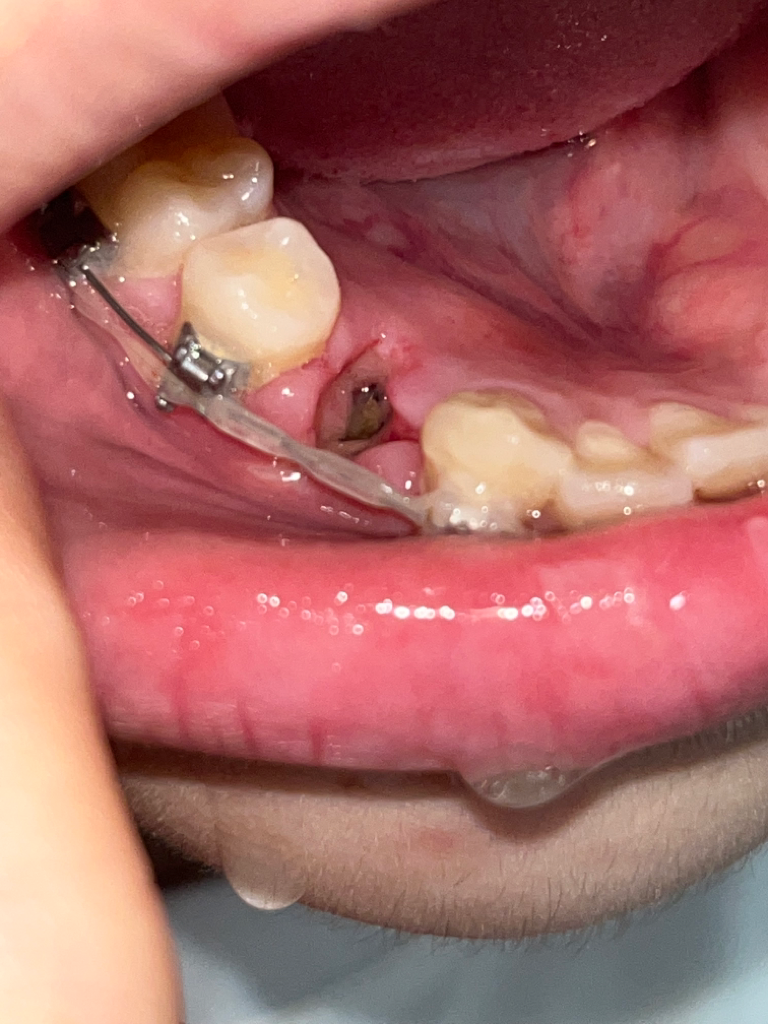

교정발치 3일차 드라이소켓인가요 ㅠㅠ

아플때마다 진통제 먹으면 괜찮아집니다 ㅜㅜㅠㅠ 근데 오늘 조심히 먹는다고 라면 먹긴했는데 그것때문일까요 ㅠㅠ?? 갑자기 어느순간부터 입안에서 역한맛이 나더니 악취가 심하게 나더라고요 드라이소켓일까요?? 병원 바로 가는게 낫겠죠?

• 1번 째 사진

사진 상 애매하기는 합니다. 통증이 극심하고 냄새도 심하게 난다면 치과를 가시는 게 좋겠습니다.

사진으로 봤을 경우에는 발치한 후에 생겨야 할 혈병이 제거된 것으로 보입니다 혈병을 제거되었을 경우 내부의 이물질이 쉽게 들어가기 때문에 냄새가 날 수 있으며 드라이 소켓이라면 해당 부의 통증이 심할 것으로 생각됩니다.

통증이 심하고 혈병이 없으며 악취가 난다면 드라이 소켓일 가능성이 있기 때문에 치과에서 진료를 받아 보는 것이 좋습니다.